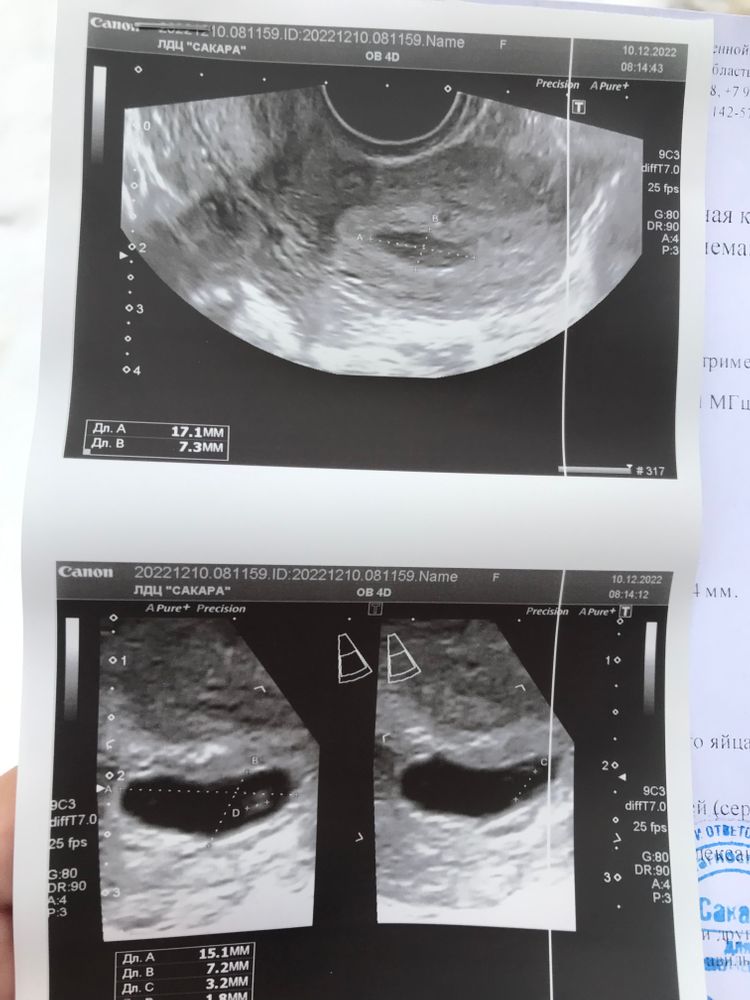

Здравствуйте. Был уже пост раньше про то, что лежала в больнице на сохранении неделю. Выписали. Сходила в платное узи 10.12.22 увидели отслойку.

Пошла на работу. На второй день, после выхода на работу, днем увидела немного мазни на прокладке (розово-коричневая). Побежала снова в больницу-испугалась. Потащили на узи 13.12.22…после моих слов о платном узи, увидели тоже отслоку…как мериют пя (не знаю…размеры с платным узи различаются сильно🤷♀️, эмбрион мерить даже не стали…узист сказал «сердцебиение есть, если заметно, поставь пока под вопросом🙈») в общем я в ужасе. Опять кололи кровоостанавивающие, хотя крови по сути почти не было, была небольшая мазня один день…я потом подумала, что может гематома выходит? Но врач мне ничего не сказала по этому поводу. Капают магнезию и дают утрожестан вагинально. Положили опять в стационар, и на долго ли? Как они поймут заживает ли отслойка или нет? Расскажите пожалуйста, как происходит заживление и как долго?